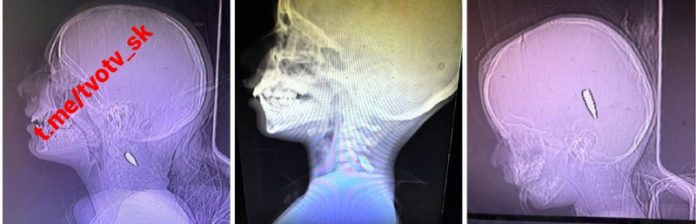

Zahrani?ní dobrovo?ní lekári, ktorí ošetrujú deti v pásme Gazy, uvádzajú, že deti boli úmyselne postrelené do hlavy, krku a hrudníka a röntgenové snímky ukázali, že bola použitá munícia kalibru 5,56 používaná Izraelskými obrannými silami, uviedol NYT.